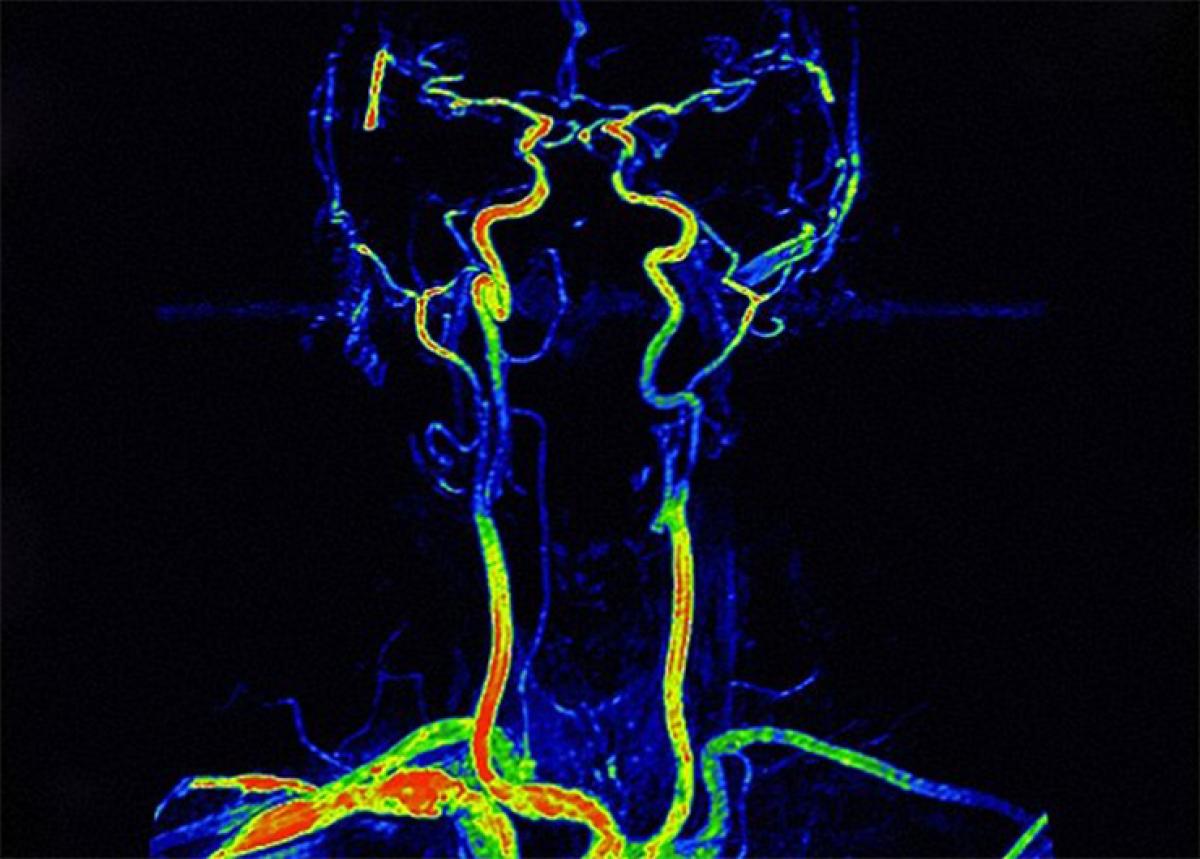

Melbourne: Intelligence in humans can be estimated by the size of the holes in the skull through which the arteries pass, says a study."It is possible to estimate brain metabolic rate from the size of the arteries that supply the brain with blood," said lead author Roger Seymour in the School of Biological Sciences, University of Adelaide.

A human brain contains nearly 100 billion nerve cells with connections measured in the trillions. Each cell and connection uses a minute amount of energy but, added together, the whole brain uses about 20 per cent of a person's resting metabolic rate. If an artery passes through a bone, then simply measuring the size of the hole can indicate the blood flow rate and in turn the metabolic rate of the organ inside.

The blood flow rate and presumably brain metabolic rate increased with brain volume much faster than expected for mammals in general. By the time of the great apes, blood flow was about 280 per cent higher than expected.